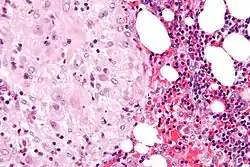

Micrograph of decidua in a lymph node. H&E stain.